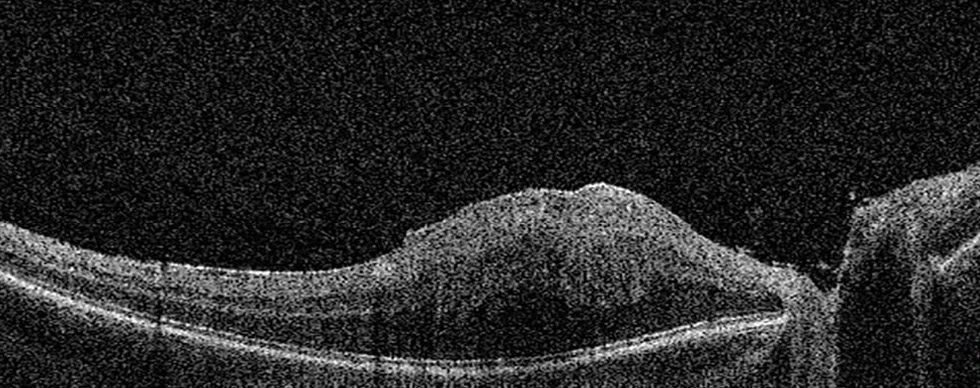

Рис. 5. Оптическая когерентная томограмма сетчатки ребёнка 4 лет с комбинированной гамартомой сетчатки и ретинального пигментного эпителия: деформация витреоретинального профиля макулярной зоны, эпиретинальная мембрана, глубокие складки сетчатки (макси-пики). Максимально корригированная острота зрения 0,03.

Fig. 5. OCT of the retina in a 4-year-old child with combined hamartoma of the retina and retinal pigment epithelium: deformation of the vitreoretinal profile in the macular zone, epiretinal membrane, deep retinal folds (“maxi-peaks”). Best corrected visual acuity 0.03.

- в шести глазах мини-пики — пилообразный рисунок витреоретинального контура или наружного плексиформного слоя [11] (рис. 4);

- в семи глазах макси-пики — складки сетчатки по всей толщине [11] (рис. 5);